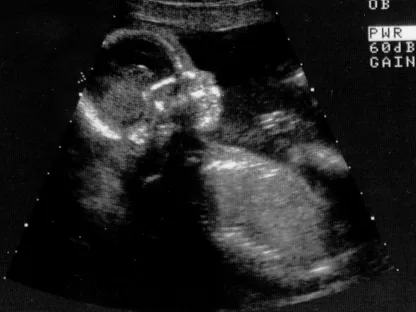

Abort